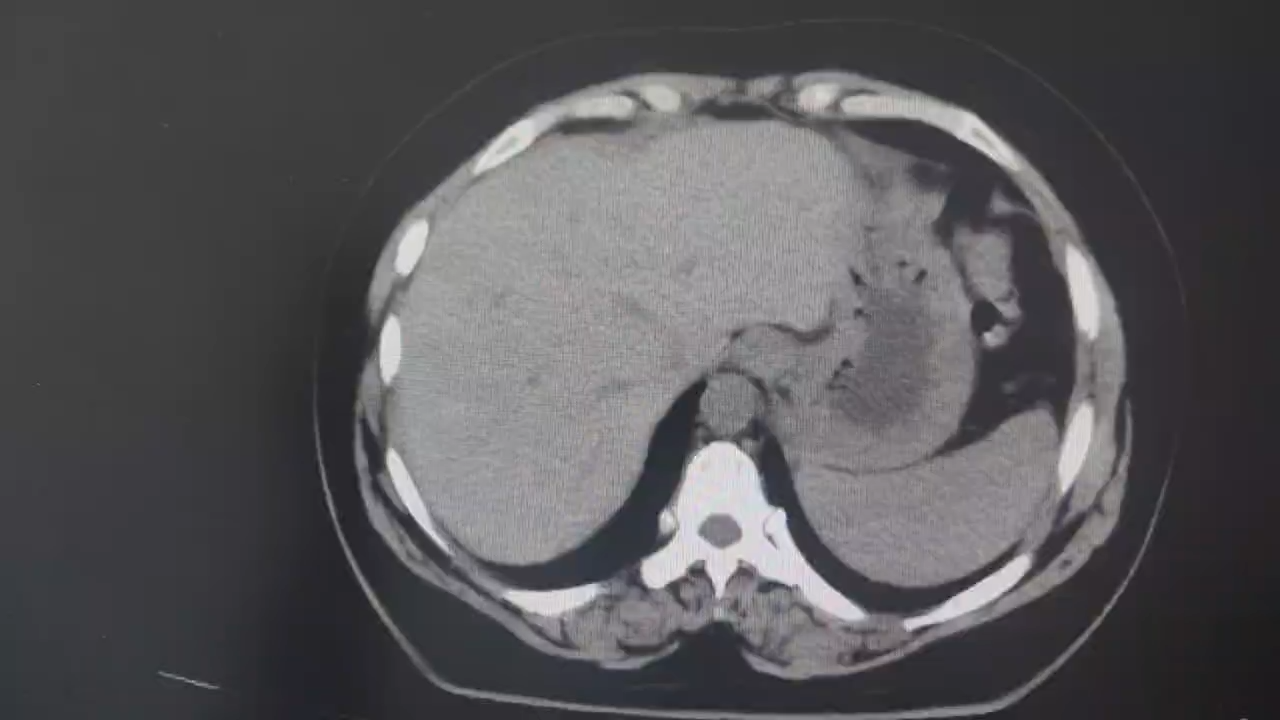

腹部增强CT检查:

平扫:

术前讨论:科室集体讨论后认为患者腹腔内肿物来源于卵巢的可能性较大,但也不排除其他来源,尤其是肠系膜来源,从腹部增强CT来看,患者腹腔内肿物供血动脉来源于肠系膜上动脉根部,即空肠第二支,空肠第一分支动脉位于肿瘤上极左侧,受压偏移明显,肠系膜上动脉及上静脉主干均明显受压变形。从CT上来看,肿瘤内没有明显强化表现,像囊性肿瘤。部分医生认为可以选择腔镜手术,先进行减压后再切除,但是考虑到这么大的肿瘤,万一是恶性的,先穿刺减压就违反了无瘤原则。最后决定备血后进行开放手术治疗。